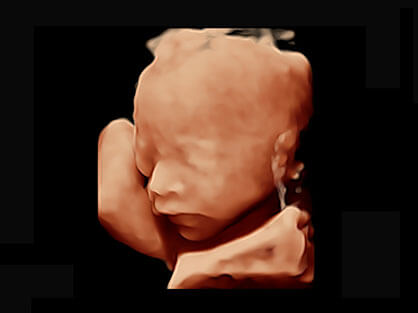

可同时显示组织结构表面和内部的轮廓信息,达到透视效果,为临床提供更丰富的诊断信息。

自动获取标准切面,自动完成测量,帮助医生快速完成检查,同时提升测量准确性。